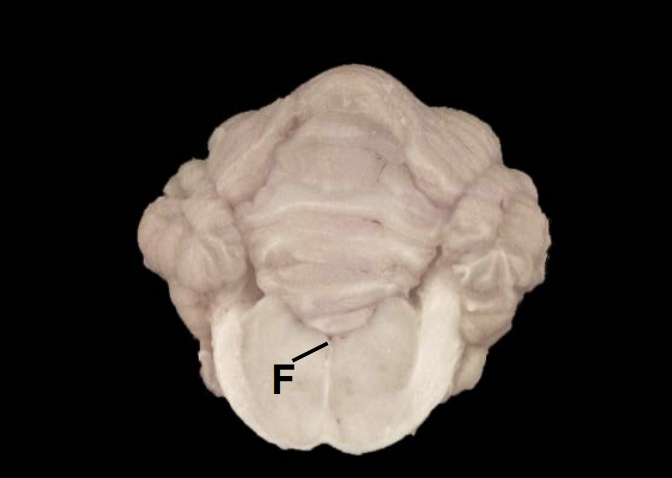

F

Fourth ventricle